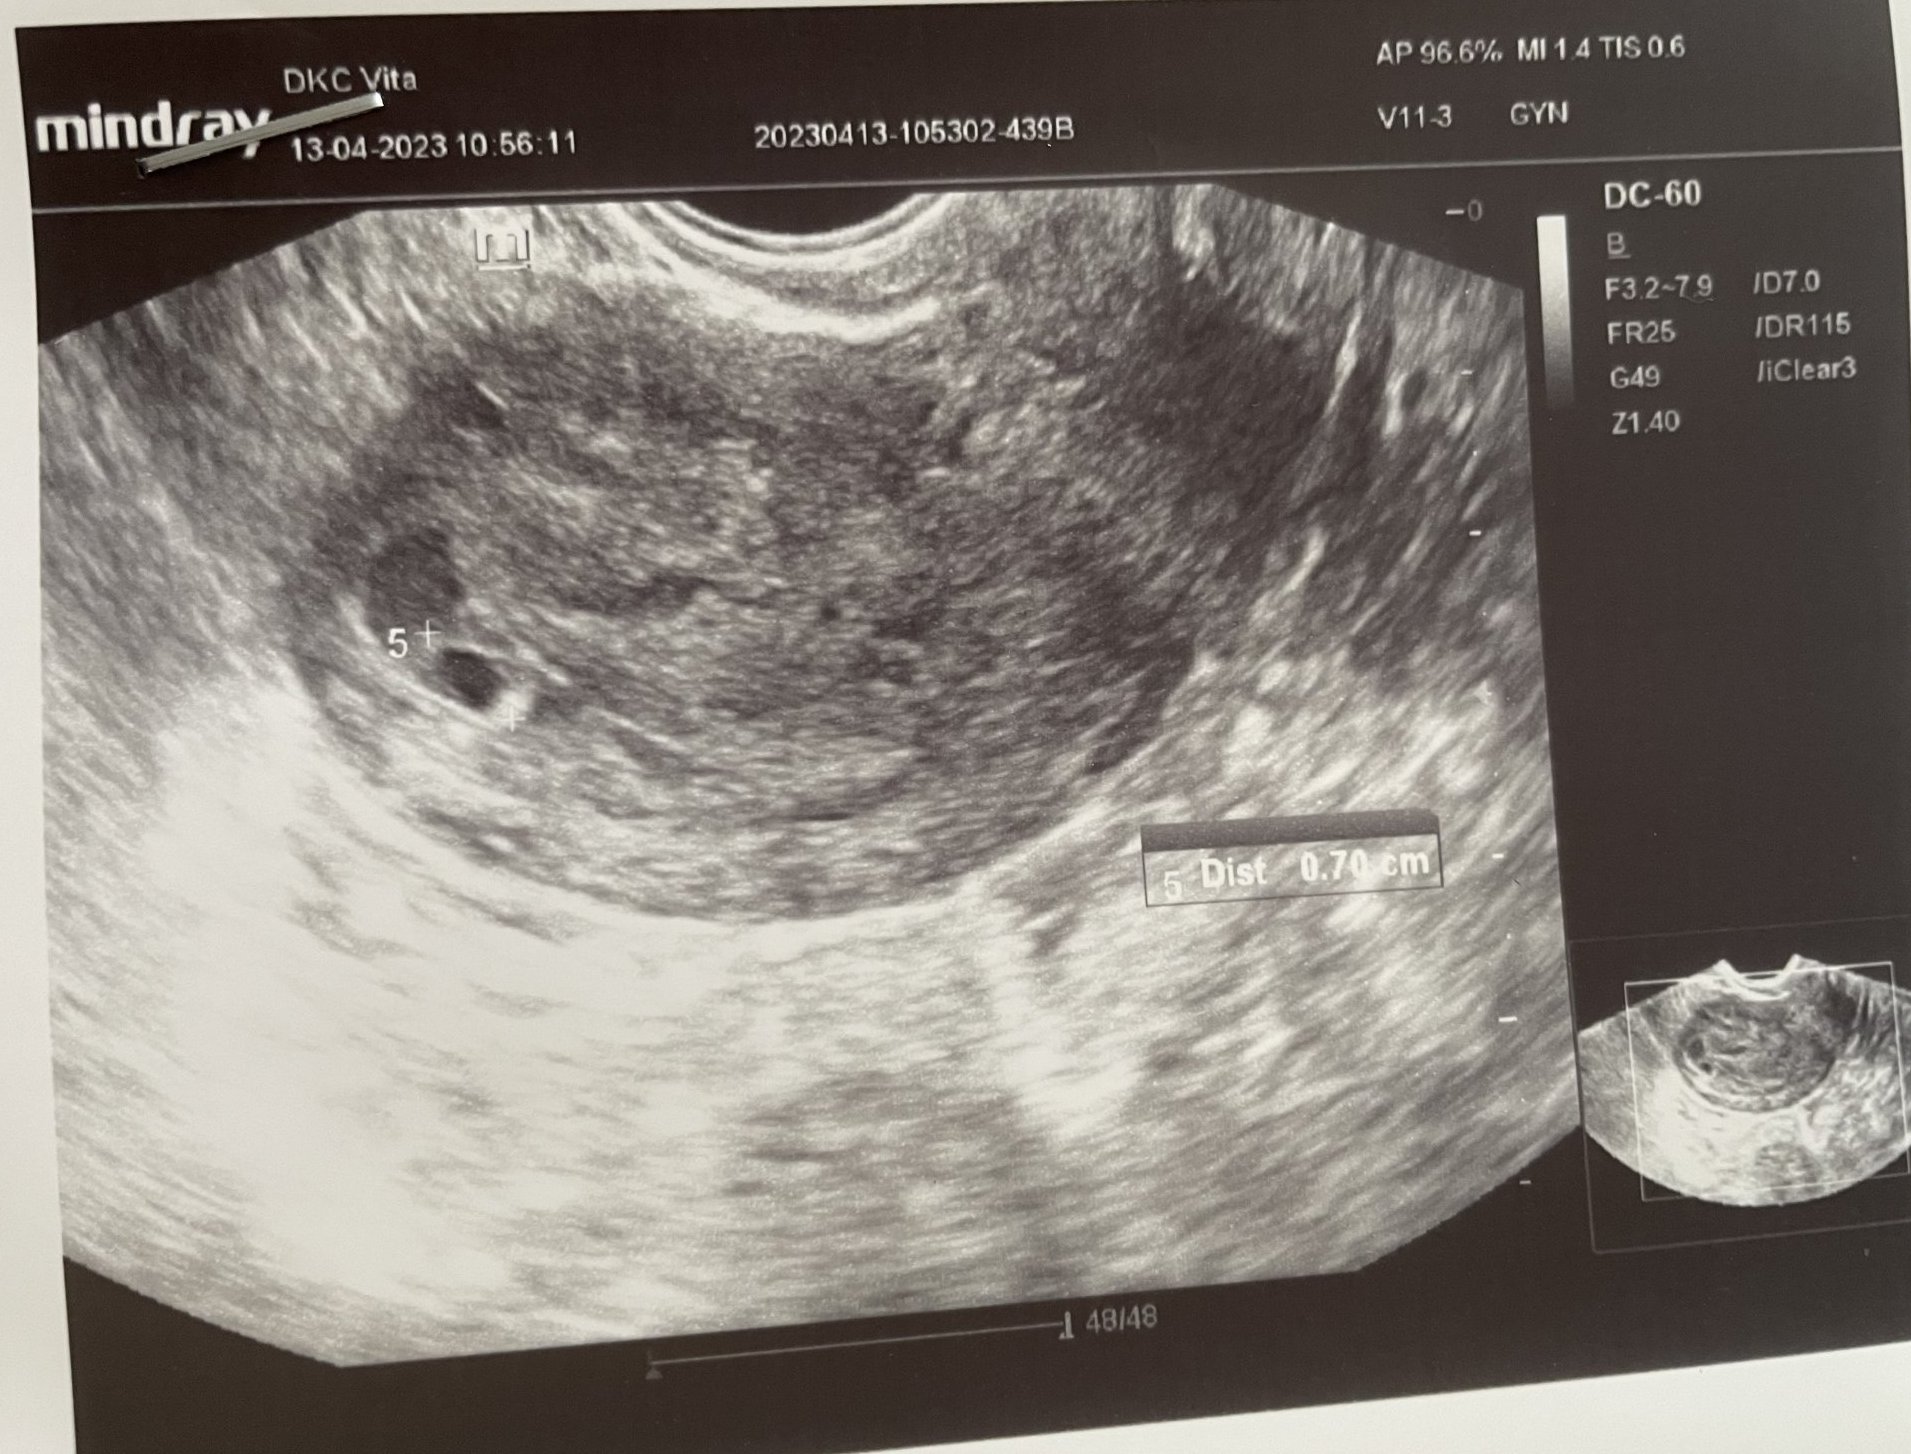

Днес бях на първи ултразвук (5гс+1) и първоначално нищо не видяха и дори се уплаших за ИБ, но в последния момент се видя много малко сакче. Измериха го 0.7 мм и ми казаха, че все още е много рано и да отида пак след 2 седмици.

Има и някаква странна сянка до него, но не разбрах какво е.